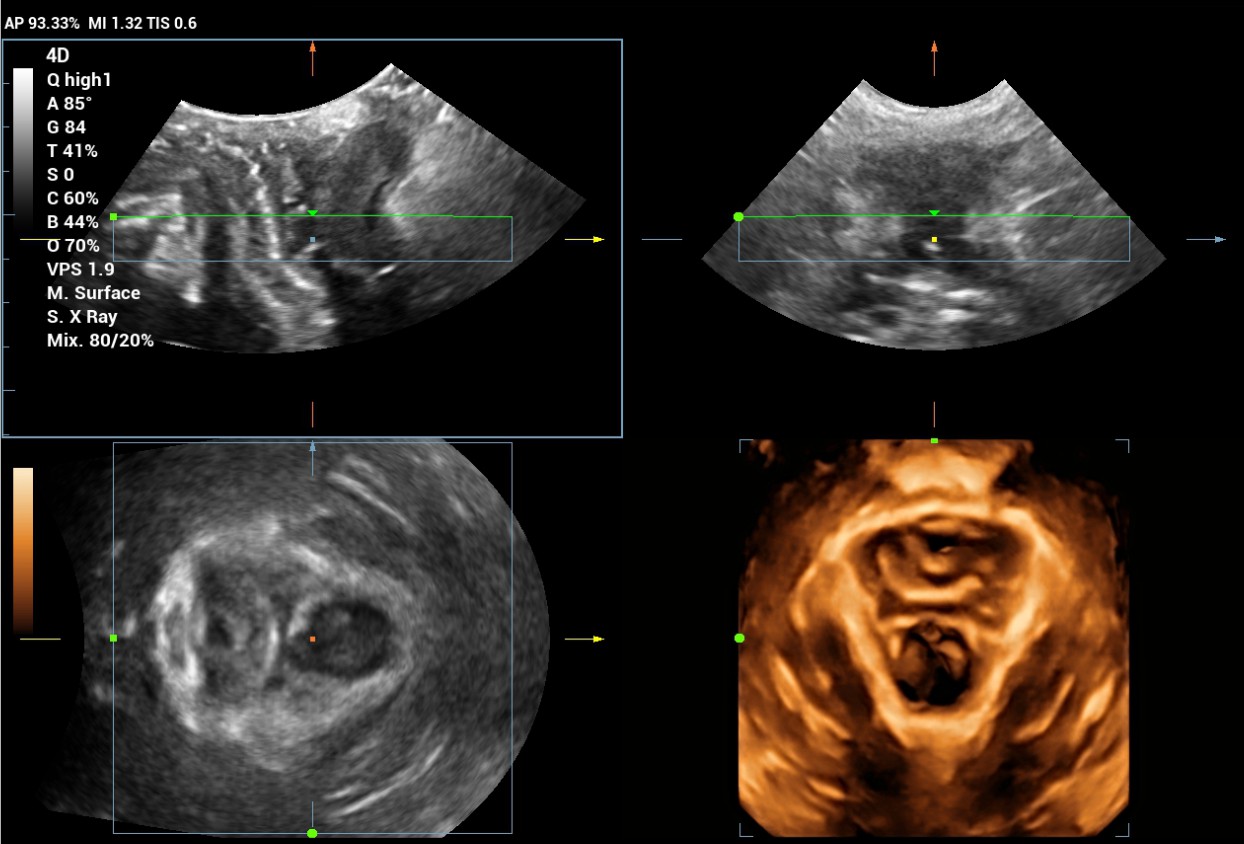

The Consona features new and concrete solutions, that efficiently help you to carry out smooth diagnoses for extensive type of patients. You will find highly powerful tools available on this series to keep you stay ahead in Obstetrics and Gynecology diagnosis.

Image Gallery